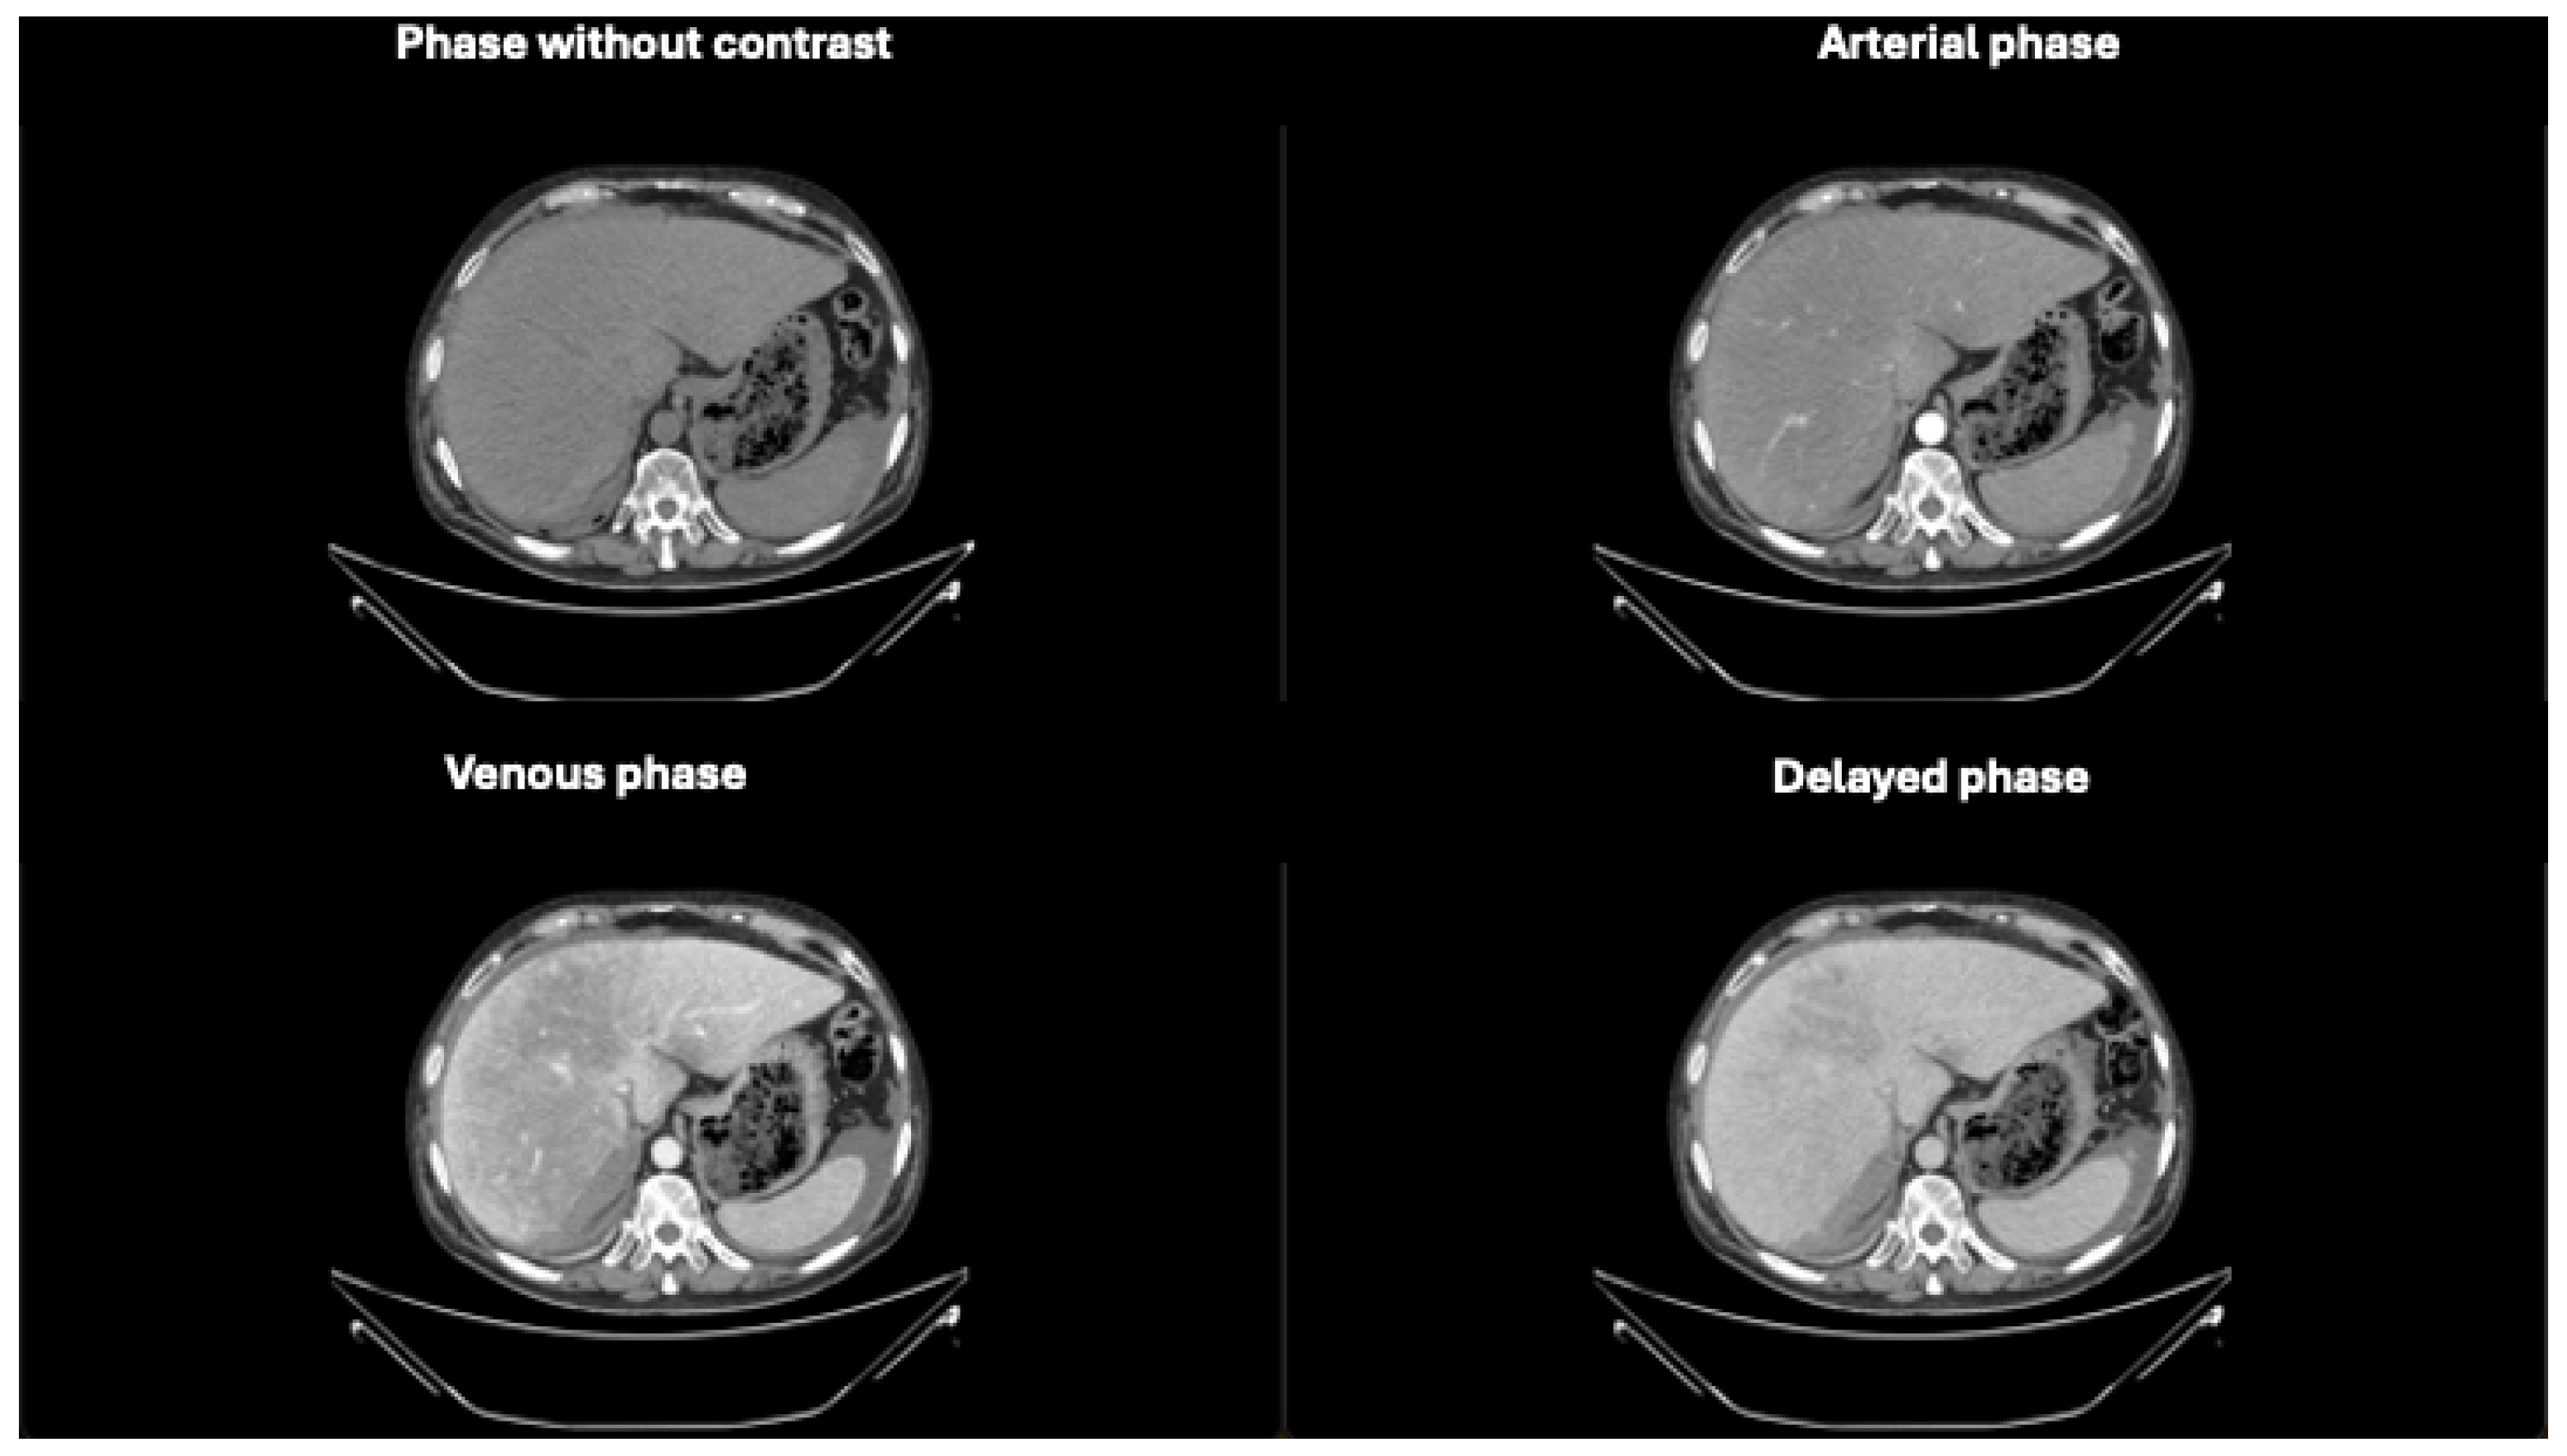

Figure 4. Axial CT images in different phases, highlighting extravasation of contrast medium within the subhepatic fluid collection. The extravasation becomes more prominent in the last phases, confirming the presence of active bleeding. The purple arrow demonstrates blood extravasation in the collection during the venous and delayed phases of the study, not visible in the baseline and arterial phases.